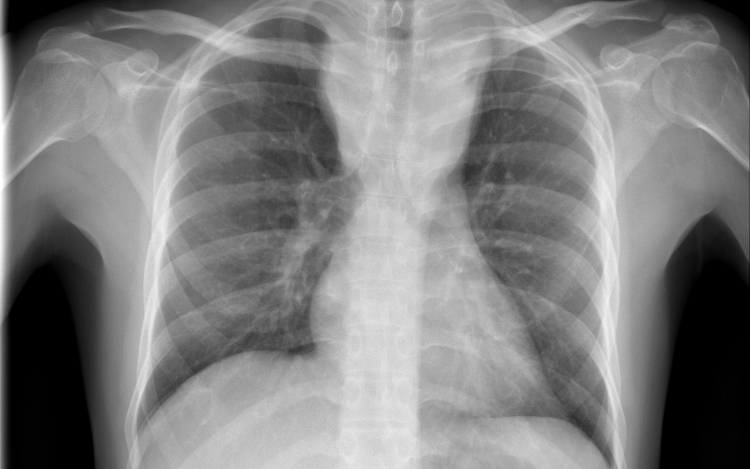

Forrás: mti - illusztráció

Tüdőrákban halt meg a transzplantáció után másfél évvel egy francia nő, akibe egy hajdan erős dohányos nő tüdejét ültették át.

A Lunc Cancer szakfolyóiratban megjelent tanulmány szerint az 57 évesen elhunyt donor 30 éven át napi egy doboz cigarettát szívott el.

A gyermekkora óta cisztás fibrózisban szenvedő páciens 2015 novemberében kapta meg a sokáig erősen dohányzó nő tüdejét, 2017 júniusában pedig bekerült a montpellier-i egyetemi klinikára, ahol két hónappal később elhunyt tüdőrákban, anélkül, hogy bármiféle terápiát alkalmazhattak volna nála. A tanulmány szerint a páciens a dohányzás okozta tüdőrák jellegzetes tüneteit mutatta.

A transzplantáció és a tüdő első rendellenességeinek röntgen általi észlelése közti rövid idő arra utal, hogy a tüdőrák már a donornál keletkezett, a szervkilökődés megakadályozására szedett immungyengítő gyógyszerek pedig csak felgyorsították a kifejlődését.

A tüdőrák hosszú lappangási idejére tekintettel a kutatók különleges elővigyázatosságot ajánlanak a dohányzó donoroktól származó szervek átültetésénél olyan esetekben, amikor a donor csak nem sokkal a transzplantáció előtt hagyott fel a dohányzással.